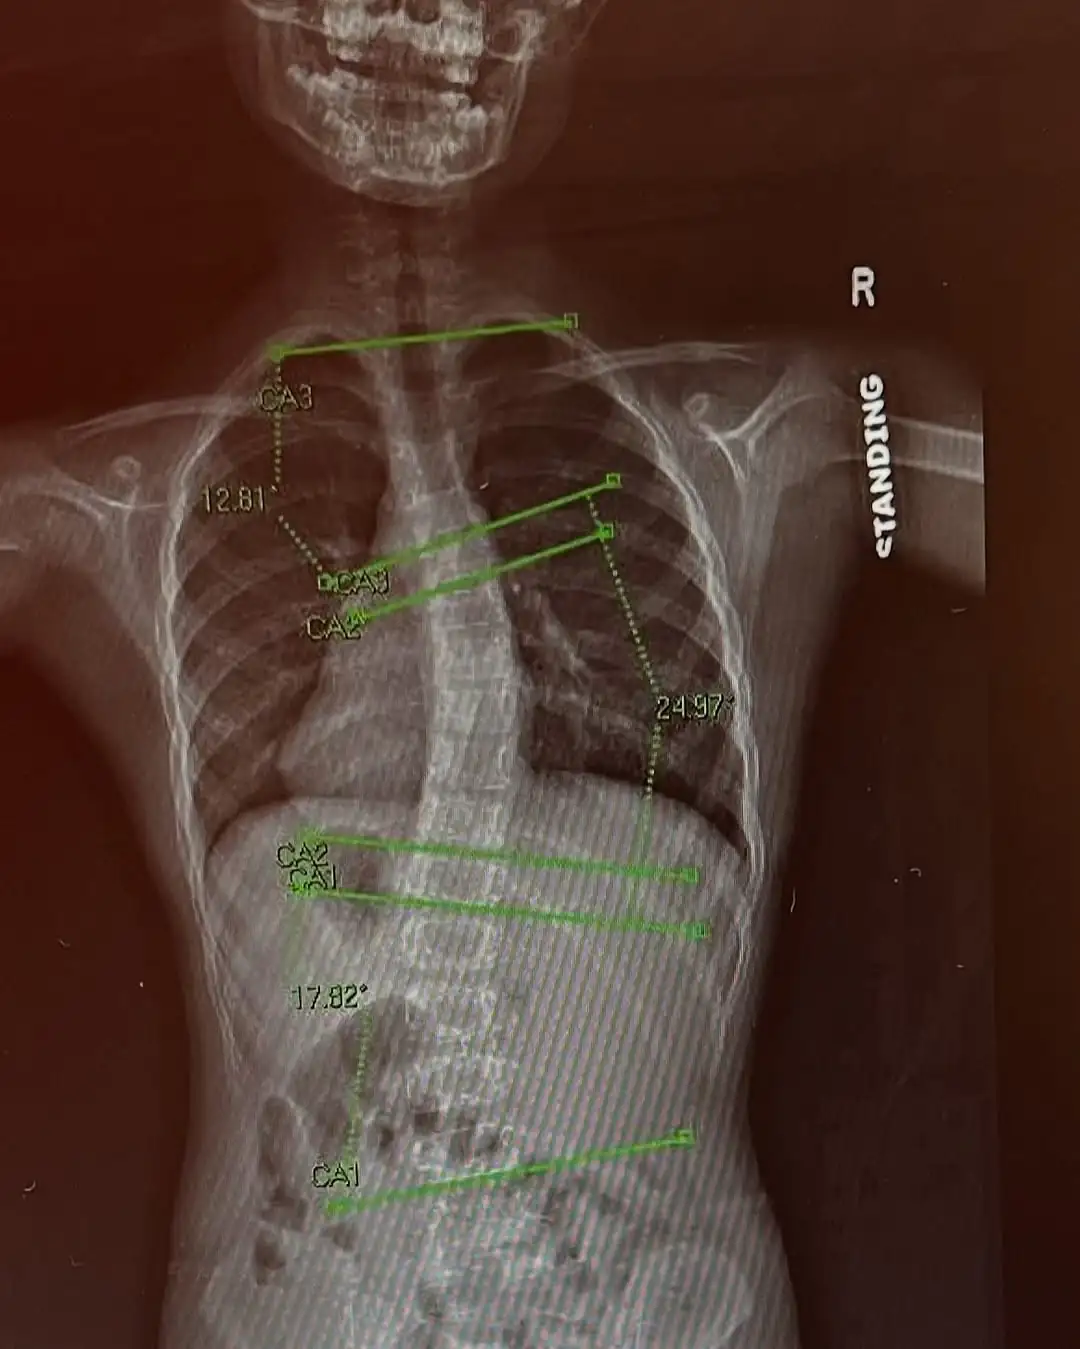

O diagnóstico de escoliose mudou a rotina da pequena Preslee Harris, de 7 anos, mas também se transformou em fonte de inspiração. Durante um exame de rotina no primeiro ano escolar, em maio de 2024, a pediatra pediu que a menina se curvasse para frente e percebeu um desvio na coluna. Exames de raio-X confirmaram o diagnóstico: escoliose, uma curvatura lateral da coluna que, no caso dela, apresentava 12 graus na parte superior, 17 no meio e 14 na inferior.

Com o encaminhamento para um ortopedista, veio a recomendação inicial de acompanhamento e novos exames após três meses. Mas, em agosto, o desvio já havia aumentado para 18 graus, o que levou os médicos a indicarem o uso de um colete ortopédico por 16 horas diárias.